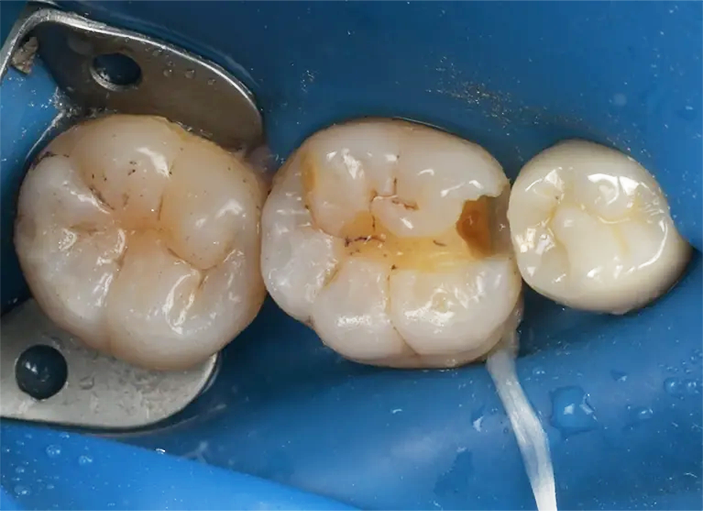

Case1

術前

ラバーダム防湿

術後

| 治療名 | ダイレクトボンディング |

|---|---|

| 治療説明 | 古い銀歯の下で虫歯が発生したため、ダイレクトボンディングを行いました。古い銀歯を除去し、ラバーダムを装着し、う蝕を除去してレジンを充填し、見た目と機能を回復しました。 |

| 治療回数・期間 | 1回 |

| 副作用とリスク | 知覚過敏症状が生じる恐れがあります。レジンが破折歯修復が必要となることがあります。 |

| 料金(税込) | 55,000円(自費) |